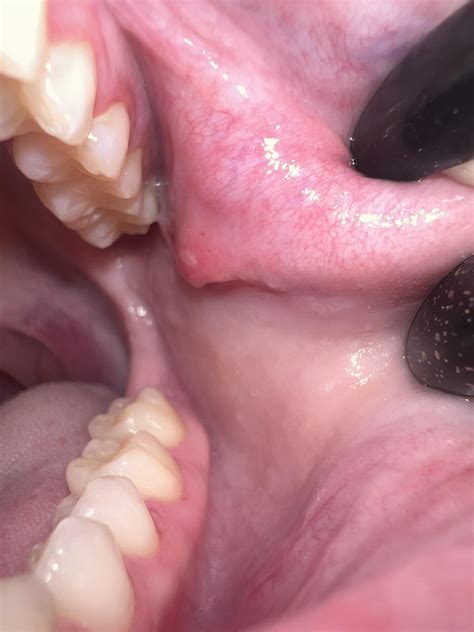

Discovering a bump in mouth can be an unsettling experience, often leading to immediate concern about oral health. Whether it is located on your tongue, gums, roof of the mouth, or inner cheek, these irregularities are surprisingly common and usually stem from benign causes. However, because the oral cavity is home to various types of tissue, identifying the underlying cause is essential for proper management and peace of mind. While most oral bumps resolve on their own, understanding when to seek professional dental or medical advice is crucial for maintaining long-term oral well-being.

The mouth is a complex environment prone to irritation and minor injuries. A bump in mouth can arise from something as simple as biting your cheek while eating to more complex issues like viral infections or tissue growths. Recognizing the characteristics of these bumps can help you determine the next steps.

• Oral Fibroma: These are smooth, pink, or skin-colored lumps that develop due to chronic irritation or trauma, such as constant biting or rubbing against jagged teeth.